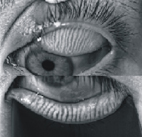

有鑑於疾病樣貌的改變,為了減少病人受檢時的不適,提高病人受檢意願及提升正確診斷率,亞東眼科憑藉著高度研發與治療敏感性,於2008年開始積極參與國內外角膜表層疾病治療新發展之學術研討會,於2012-2015年與陽明大學醫工所及漢唐光電公司合作,開發乾眼症紅外線熱像輔助診斷系統,並積極進行臨床研究,目前該系統已取得美國FDA及本國TFDA核准量產,為全國唯一、全球唯二的非接觸性紅外線熱像乾眼瞼查儀,更於2014年第四季引進乾眼脂液檢查儀(如:圖一),為全國第一家正式引進乾眼脂液檢查儀的醫學中心,提供民眾進階診療。乾眼脂液檢查儀配合瞼板腺紅外線圖像(meibography)偵測後以圖像方式呈現病人瞼板腺萎縮程度,同時記錄病人不完全眨眼比率,不完全眨眼比率會導致瞼板腺分泌降低,直接影響淚膜中脂質厚度,除了導致異物感、視力模糊等乾眼症狀之外,不完全眨眼也將導致眼瞼腺板開口阻塞,最終引發眼瞼腺萎縮(如:圖二),成為不可逆的結果。透過這些明確的檢查結果報告,讓病人清楚了解造成其本身乾眼症的主要原因,進而能夠藉由眼瞼清潔熱敷、眨眼訓練等物理治療及併用特定藥物治療,有效的提高治療成效。

圖二、正常的瞼板腺

圖二、瞼板腺萎縮(紅色箭頭)